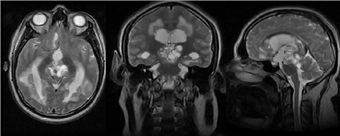

Imagen 2 Imagen heterogénea compleja en región rostral de 4to ventrículo con extensión a unión diencéfalo-mesencefálica, periventricular y cambios en sustancia blanca asociados a ventriculomegalia de 3er ventrículo y ventrículos laterales.